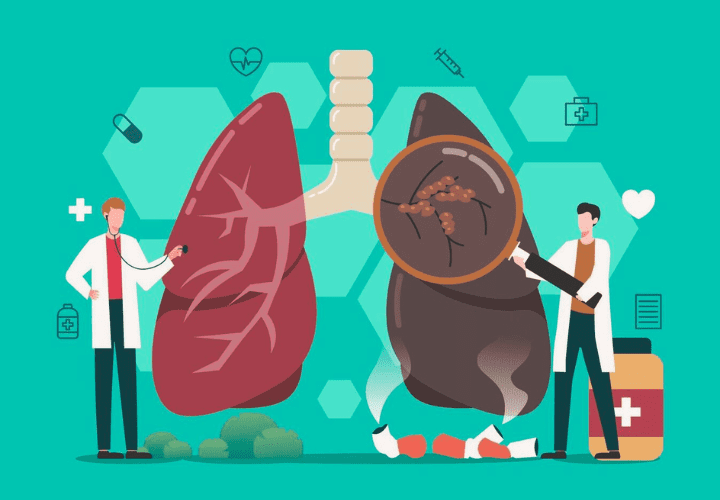

Our Pulmonary & Respiratory Services

At our practice, we provide comprehensive, evidence-based respiratory care for patients with both common and complex lung conditions. Led by Dr. Srinivas Rajagopala, a senior pulmonologist and lung transplant specialist in Chennai, our services are designed to deliver accurate diagnosis, advanced treatment, and long-term outcomes.

Interstitial Lung Disease (ILD)

Interstitial Lung Disease (ILD) is a group of lung conditions that cause inflammation and scarring, leading to increasing breathlessness.

Early diagnosis and proper care can help slow the disease and improve quality of life